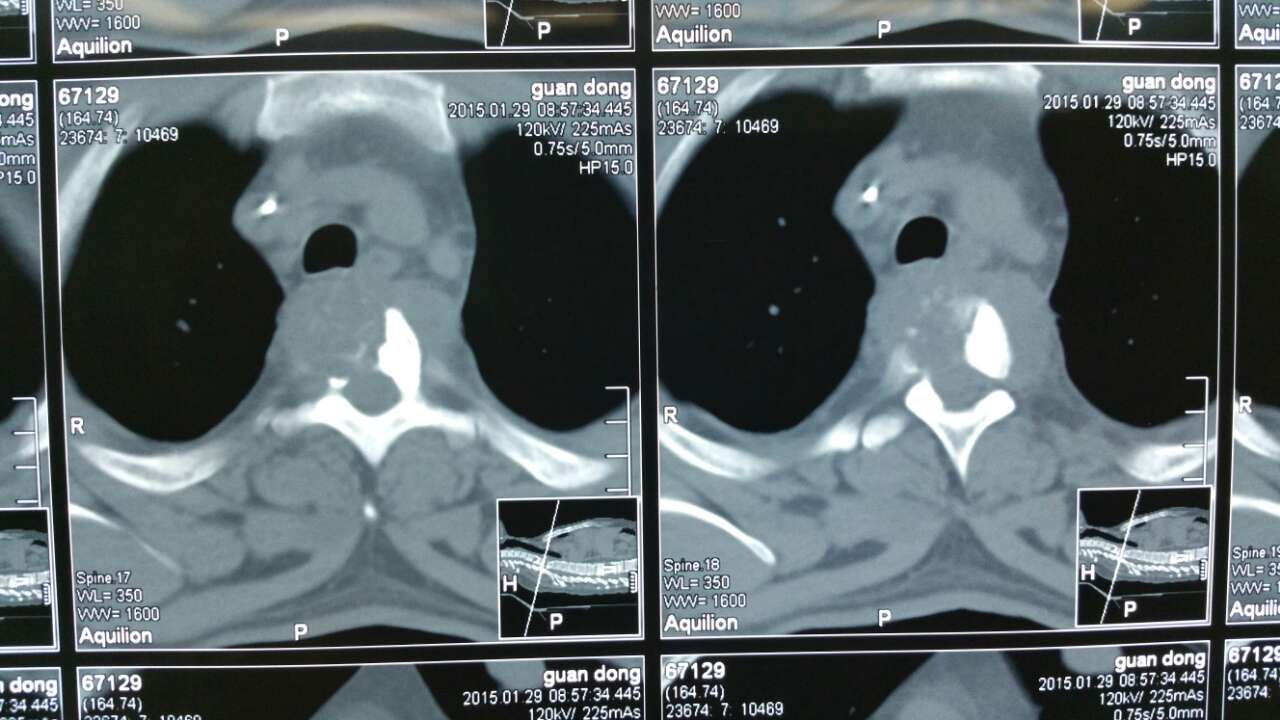

该患者为69岁女性,磁共振显示为胸椎异常信号,考虑胸椎结核.

乙胺丁醇四联抗结核治疗3周后,行前路病灶清除植骨内固定术:胸椎ct